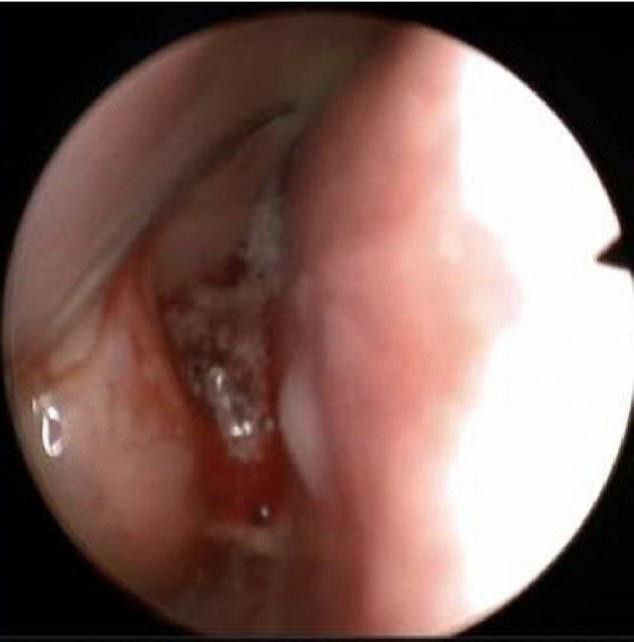

Sau khi chụp X-quang và CT, các bác sĩ đã phát hiện ra rằng có một vật thể lạ trong xoang mũi của cô gái. Hình ảnh quét CT cho thấy đây là “một vật thể lớn, có hình dạng bất thường, bao gồm nhiều gai và cánh”, được các bác sĩ mô tả giống như “đá san hô”.

Khi được lấy ra, các bác sĩ nhận thấy đó là một miếng cao su được phủ chất nhầy dài khoảng 2cm, có mùi hôi rất khó chịu.

Miếng cao su đã bị mắc kẹt trong mũi cô từ khi còn nhỏ, dù cô không có kí ức nào về việc tại sao nó lại ở đó. Và miếng cao su đã trở thành “nhân”, được các chất lắng đọng bao bọc trong suốt nhiều năm và trở thành sỏi mũi.

Sự phát triển kì lạ của sỏi mũi thường dẫn đến những chẩn đoán sai. Bác sĩ Mohiyuddin Ali tại Bệnh viện Ain Alkhaleej - người trực tiếp điều trị cho cô gái cho biết: “Nữ bệnh nhân không có bất kì triệu chứng nào của việc mắc sỏi mũi, kể cả đau đầu.”